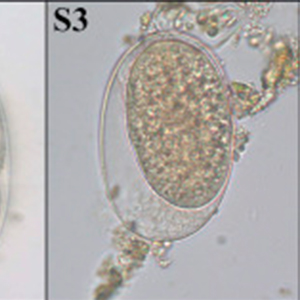

Les œufs de strongle présentent globalement la même morphologie ; ce sont des œufs ovalaires, à paroi lisse, possédant une morula et des faces latérales non parallèles. Leur taille est très variable (40 x 60 μm à 110 x 230 μm) et les groupes évoqués ci-dessus peuvent présenter des caractéristiques permettant d’orienter le diagnostic mais ces dernières sont à prendre avec précaution. Ces œufs, lorsqu’ils persistent longtemps dans le milieu extérieur, peuvent présenter un embryon vermiforme (Garcia, 2021).

- Les anguillules(Strongyloides): ces nématodes rentrent dans le diagnostic différentiel des œufs de strongle embryonnés. A l’inverse des œufs de strongles, ils mesurent 40-70 μm de longueur pour 20-35 μm de largeur, possèdent une paroi très fine et leurs faces latérales sont parallèles (Garcia, 2021).